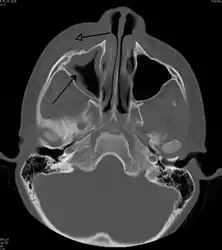

A CT scan showing sinusitis of the ethmoid sinus

For sinusitis lasting more than 12 weeks, a CT scan is recommended.[47] On a CT scan, acute sinus secretions have a radiodensity of 10 to 25 Hounsfield units (HU), but in a more chronic state they become more viscous, with a radiodensity of 30 to 60 HU.[49]